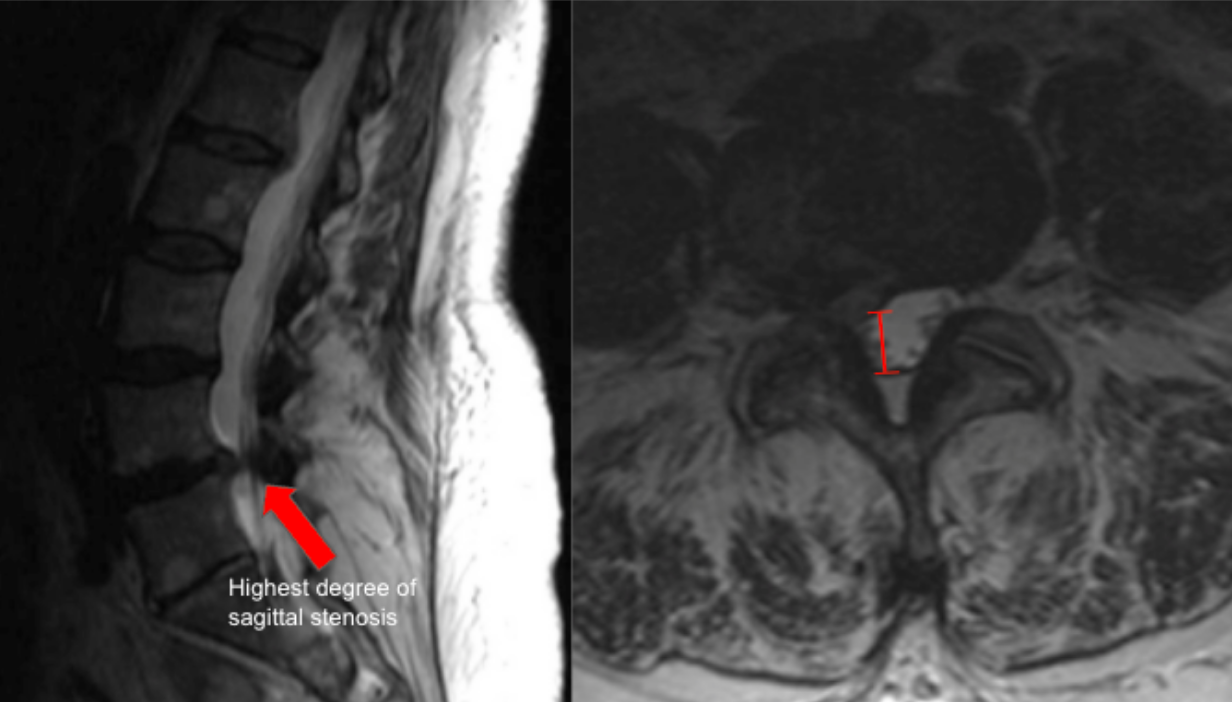

Lumbar AP canal diameter quantifies the anteroposterior dimension of the central spinal canal and is a standard morphologic measurement for diagnosing lumbar spinal stenosis. It reflects the available space for the cauda equina and is reduced by disc bulge, facet hypertrophy, ligamentum flavum thickening, or spondylolisthesis.

This measurement is most reliable on axial T2-weighted MRI, where cerebrospinal fluid provides natural contrast.

• Use the sagittal MRI to identify the disc level of maximal stenosis.

• Scroll to the corresponding axial T2 slice at that level.

• Identify:

• The posterior margin of the vertebral body or disc (anterior boundary).

• The anterior margin of the ligamentum flavum or lamina (posterior boundary).

• Draw a straight line between these two points along the midline of the canal.

• Measure this distance in millimeters (mm) — this is the AP canal diameter.